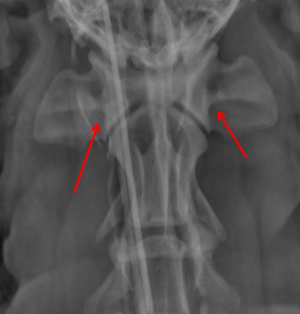

ID radiographic view

VD

ID.

Mandible